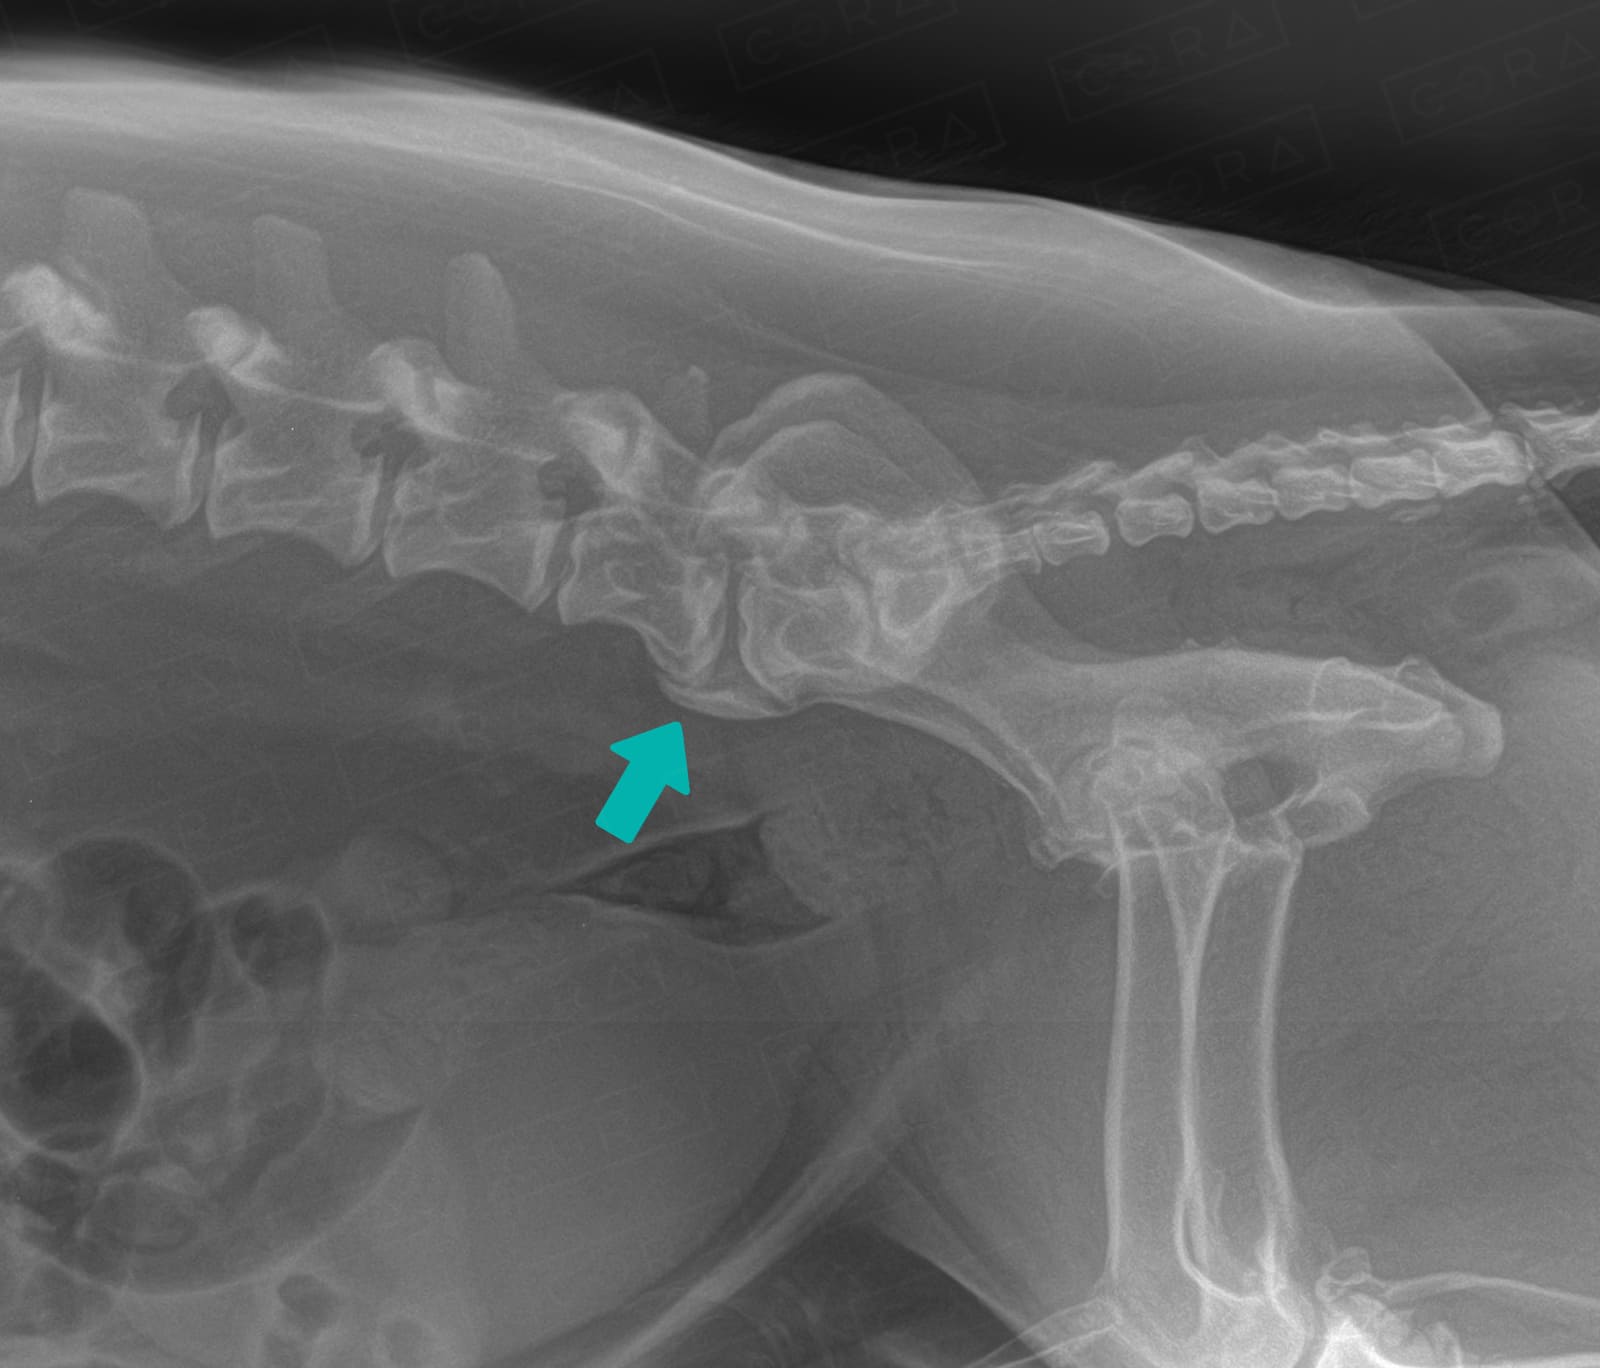

Devido à instabilidade crônica, com frequência é notada uma espondilose ventral, popularmente conhecida como "bico de papagaio".